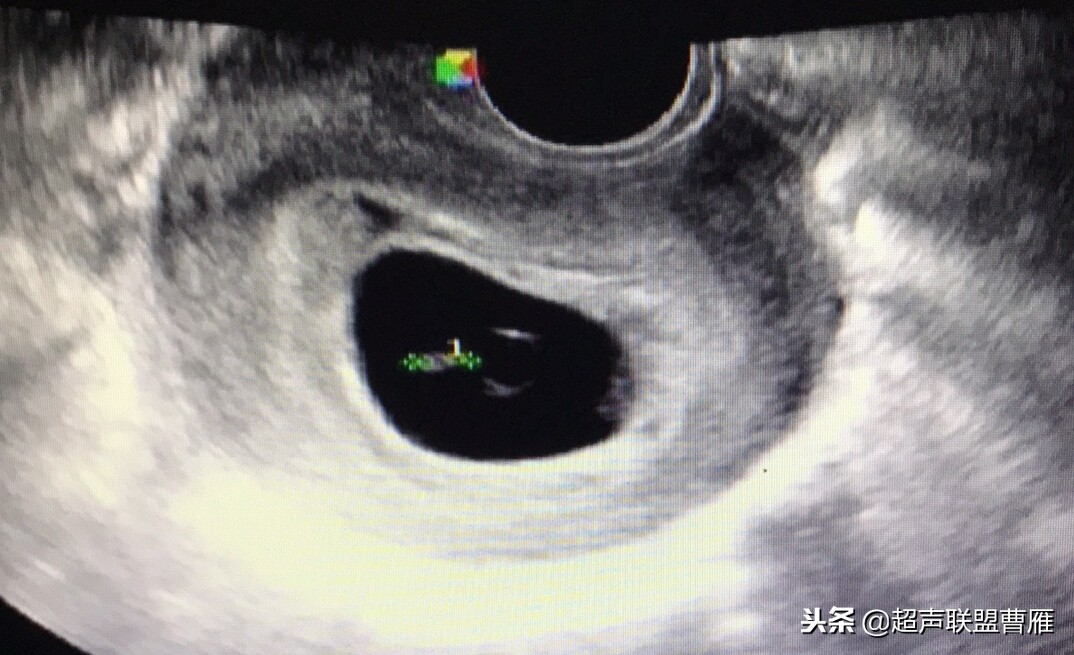

· 当孕囊>20mm时多次寻找及反复不能发现卵黄囊 则可能是枯损卵或预示为不良胚胎

妊娠8周以后,妊娠囊直径在20mm以上,未见卵黄囊,基本上没有活胎。

妊娠囊 28mm, 未见卵黄囊,hCG 500miu/L ,夭折。

孕囊20mm,没有卵黄囊及胚体影像,应系死胎 。

卵黄囊消失